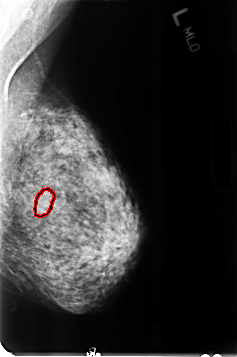

ics_version 1.0 filename B-3357-1 DATE_OF_STUDY 25 7 1995 PATIENT_AGE 55 FILM FILM_TYPE REGULAR DENSITY 3 DATE_DIGITIZED 13 7 1998 DIGITIZER LUMISYS LASER SEQUENCE LEFT_CC LINES 4664 PIXELS_PER_LINE 3096 BITS_PER_PIXEL 12 RESOLUTION 50 OVERLAY LEFT_MLO LINES 4640 PIXELS_PER_LINE 3080 BITS_PER_PIXEL 12 RESOLUTION 50 OVERLAY RIGHT_CC LINES 4608 PIXELS_PER_LINE 3072 BITS_PER_PIXEL 12 RESOLUTION 50 NON_OVERLAY RIGHT_MLO LINES 4624 PIXELS_PER_LINE 3096 BITS_PER_PIXEL 12 RESOLUTION 50 NON_OVERLAY |

FILE: B_3357_1.LEFT_MLO.OVERLAY TOTAL_ABNORMALITIES 1 ABNORMALITY 1 LESION_TYPE MASS SHAPE OVAL MARGINS CIRCUMSCRIBED-OBSCURED ASSESSMENT 4 SUBTLETY 2 PATHOLOGY BENIGN TOTAL_OUTLINES 1 BOUNDARY |